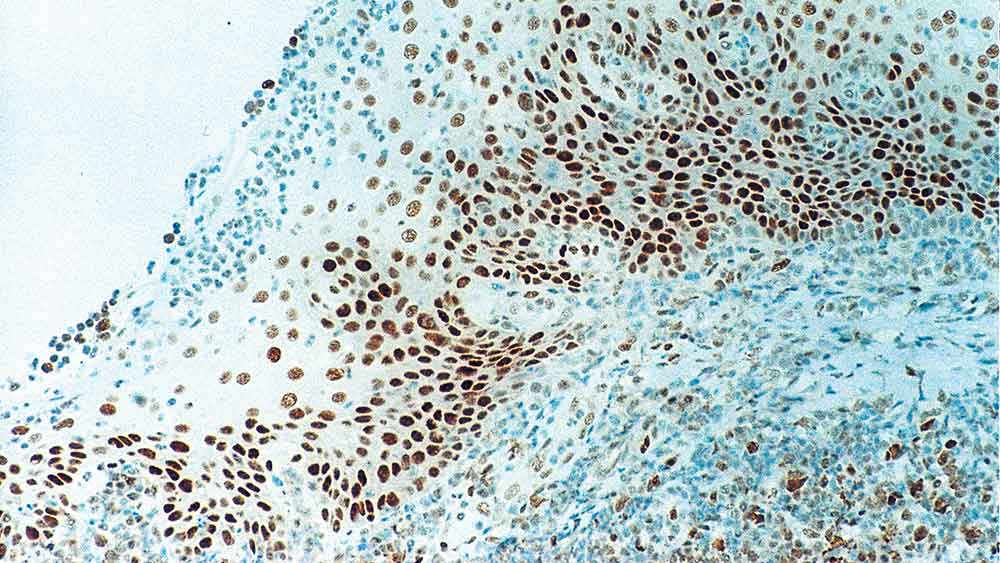

Human tonsil: immunohistochemical staining for Retinoblastoma Gene Protein. Note intense nuclear staining of epithelial cells. Retinoblastoma Gene Protein: clone 13A10

视网膜母细胞瘤(Rb)是一种罕见的视网膜肿瘤,与13号染色体突变有关。Rb抑癌基因编码的核磷酸化蛋白存在于许多细胞中,可能通过激活转录因子ATF-2间接调控细胞生长。激活ATF-2发起的TGF-β2的表达,进而影响细胞生长抑制基因转录。Rb基因的双侧突变可能在多种恶性肿瘤的发生发展中起重要作用。产物特异性信息NCL-RB-358被提至Rb基因蛋白的n端区域。